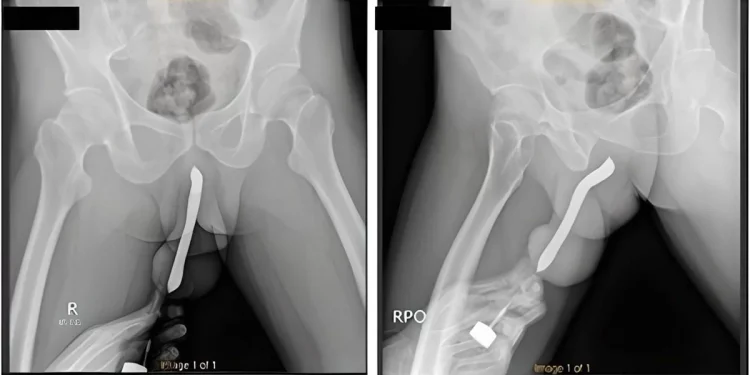

O homem ainda esperou cerca de 12 horas após o acidente para procurar ajuda médica. Os profissionais do Hospital Geral Acadêmico Soetomo, na cidade de Surabaya, descrevem que a situação do pênis era complicada. O órgão estava, além de inchado, muito deformado por conta da escova que ainda estava dentro.

O homem admitiu aos socorristas do hospital que colocou a escova por “satisfação pessoal”. Ele já havia adiantado que fez um pequeno corte no órgão. Ele teria como finalidade facilitar a introdução de mais objetos no órgão. A “anomalia” foi feita em 2017, entretanto não foi informado se a escova estava dentro desde então.

O indonésio precisou passar por uma cirurgia de duas horas para retirada da escova. Ele recebeu alta 3 dias depois e não sofreu complicações, conseguindo urinar normalmente. Embora não tenha ossos, o pênis tem tubos esponjosos que enchem de sangue, deixando ele ereto. As fraturas são super comuns nesta região.